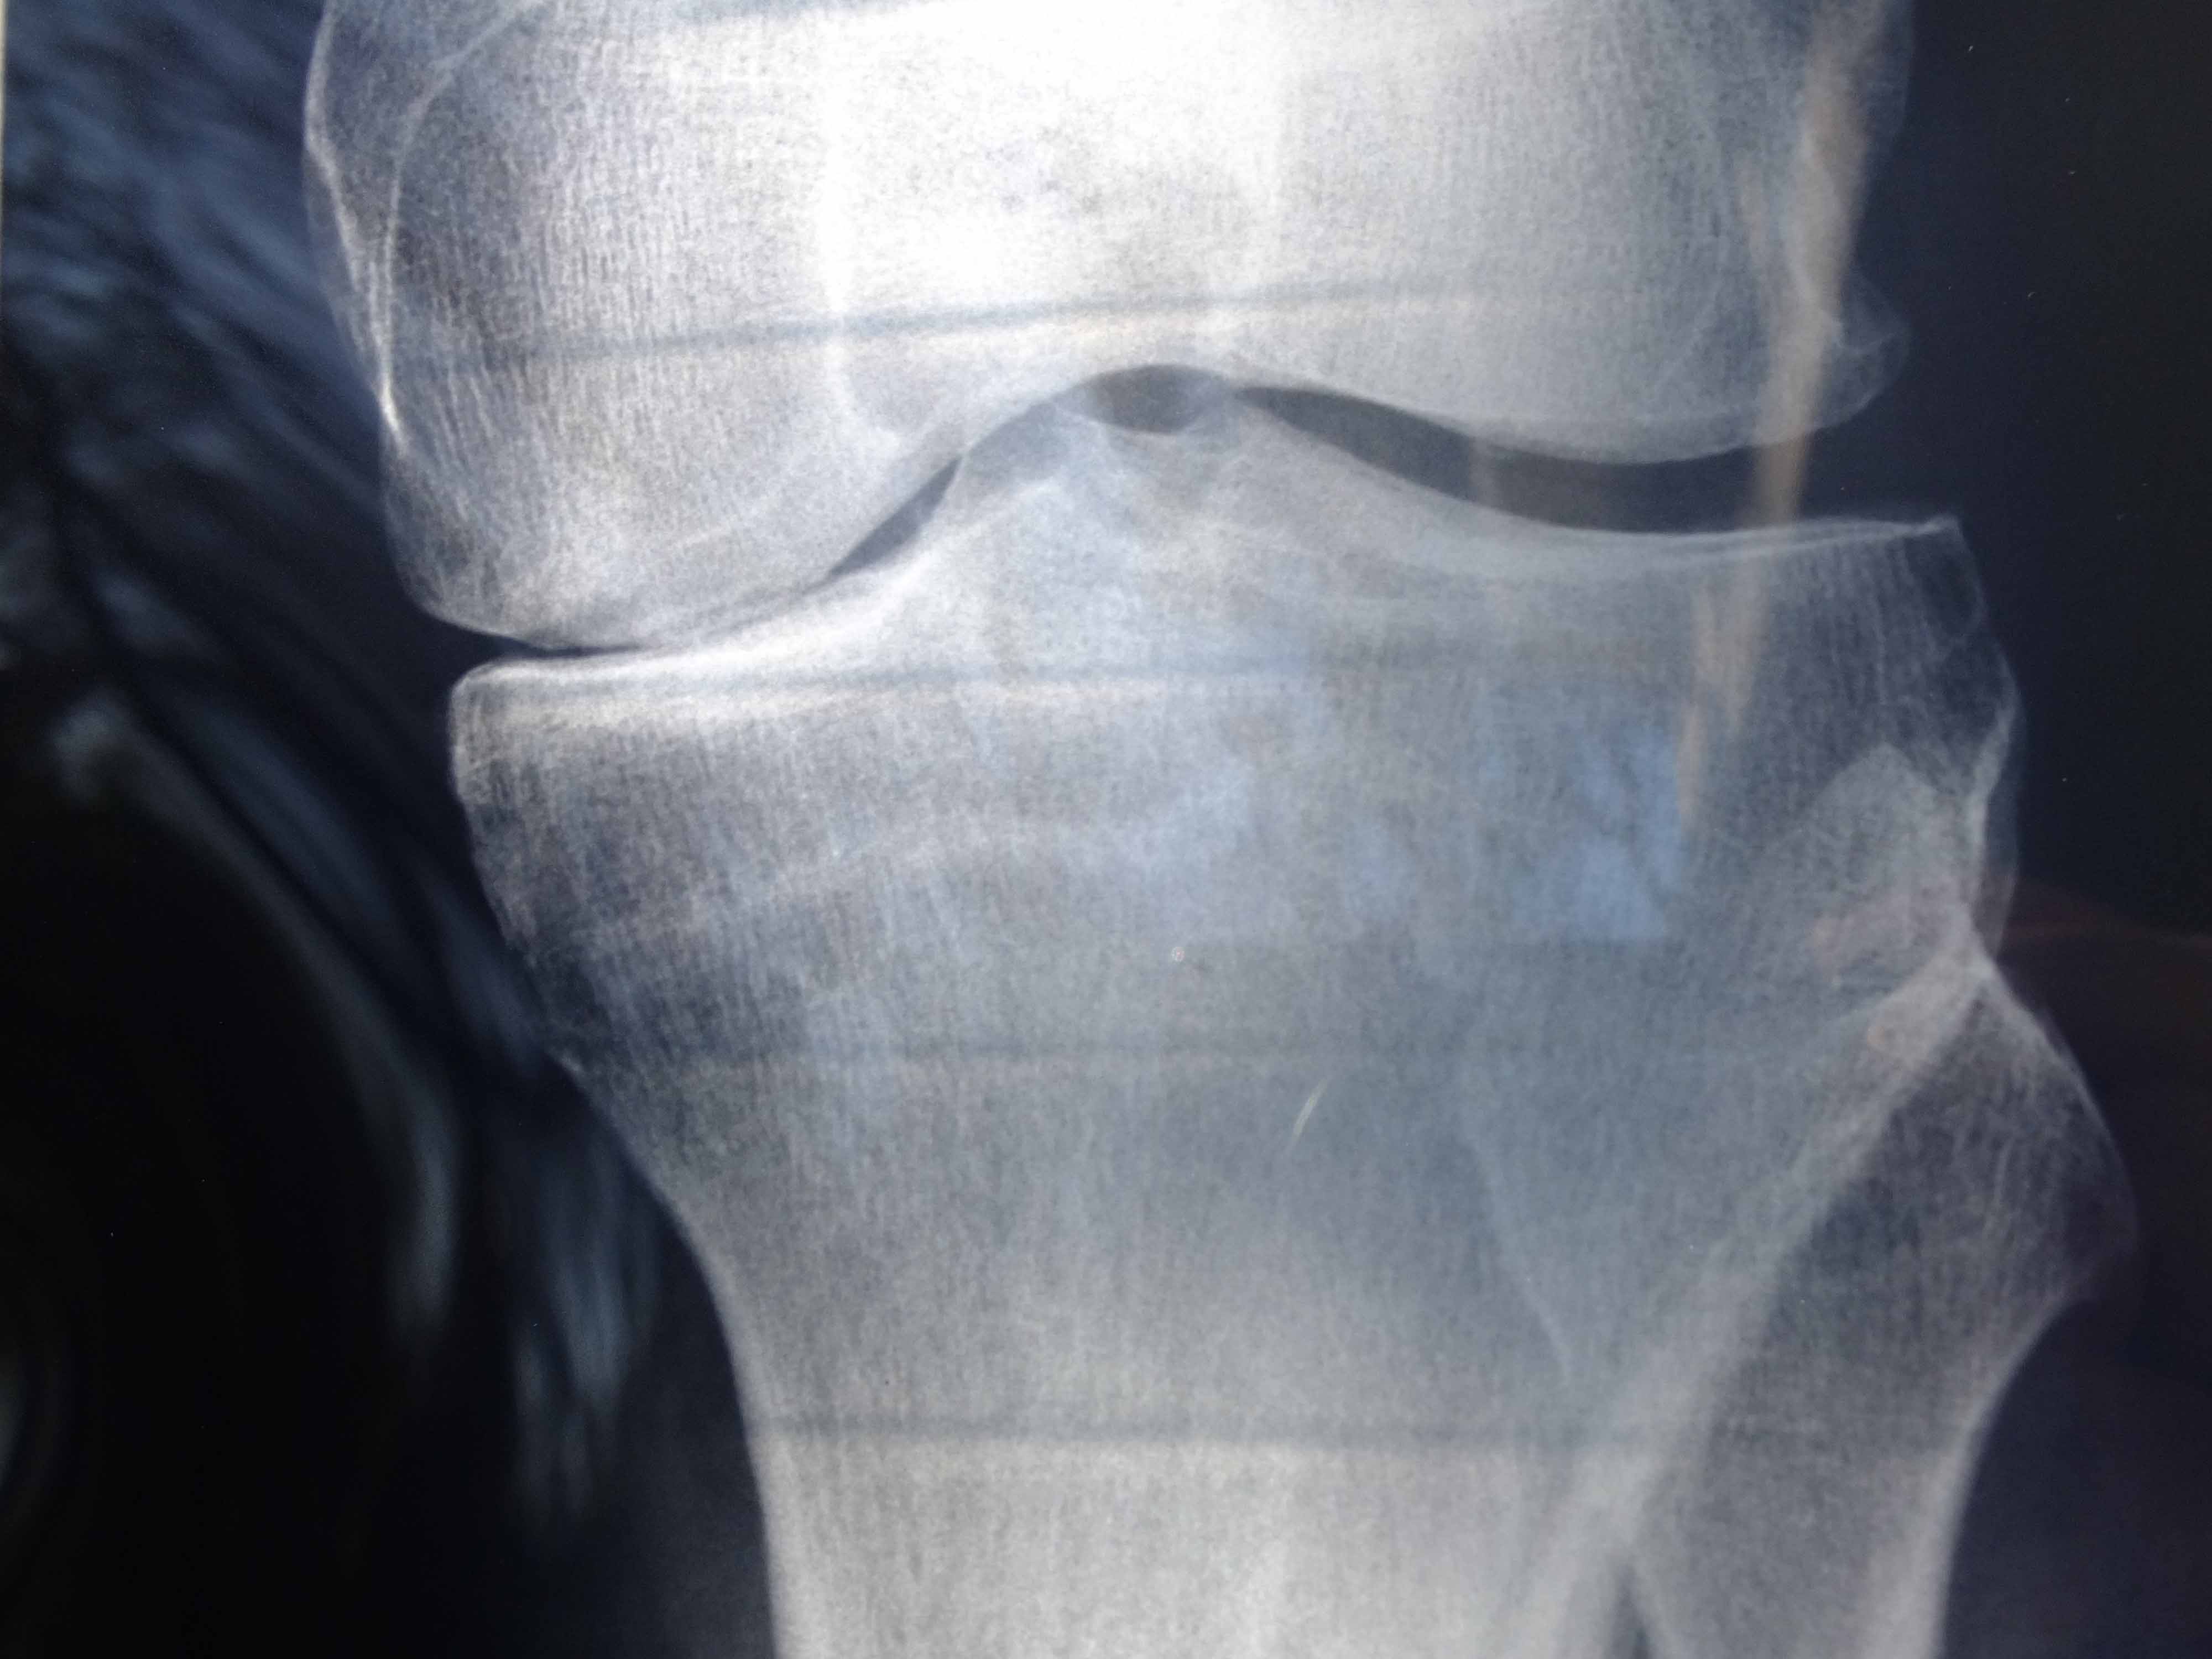

Because I walked those kms on a knee that doctors told me needs replacement.

As some of you who follow this blog might know, I have bad knee issues. On my first Camino I walked in extreme pain, and only completed the pilgrimage on painkillers.

Later, after an MRI, I was told I was bono-a-bono; that is, bone on bone – and that a knee replacement wasn’t a matter of if, it was a matter of when.

According to my surgeon I have no cartilage in my knee joint.

Zero.

Zilch.